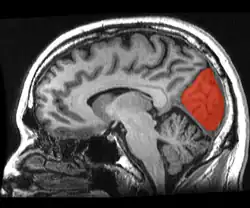

![]() Sagittal MRI slice with the cuneus and lingual gyrus shown in red. | |

The cuneus (from Latin 'wedge'; pl.: cunei) is a smaller lobe in the occipital lobe of the brain. The cuneus is bounded anteriorly by the parieto-occipital sulcus and inferiorly by the calcarine sulcus.